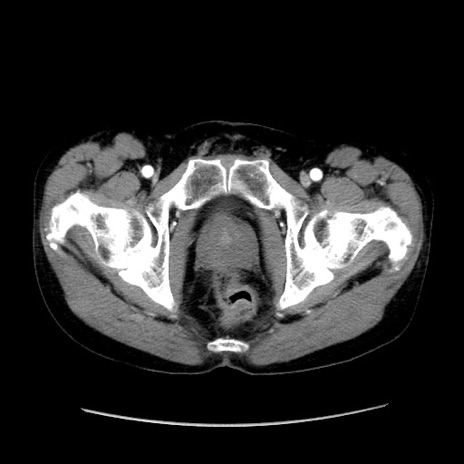

症例37(横断像)

【症例】40歳代 男性

【主訴】腹痛

【現病歴】4時間ほど前に電車に乗車中に臍部上より腹痛出現。徐々に増悪し起立困難となり、救急外来受診。生ものは数日食べていない。今朝お雑煮を食べた。

【身体所見】BT 36.8℃、BP 117/84mmHg、HR 91/min、SpO2 97%、苦悶様、腹部:臍上部広範囲圧痛あり、反跳痛±

【データ】WBC 8100、CRP 0.03